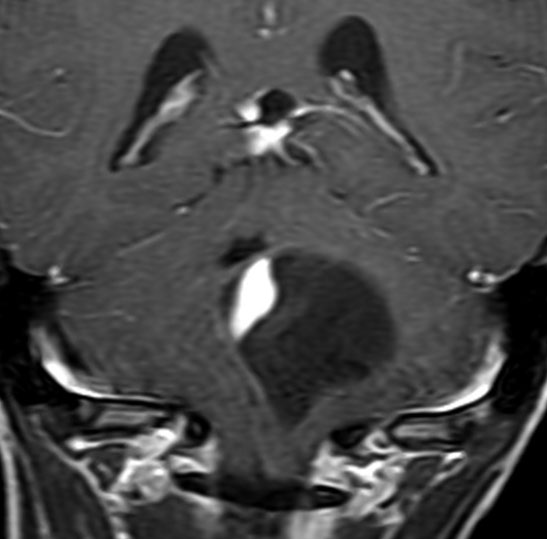

眼窩内に限局する視神経膠腫:神経鞘腫と鑑別が難しいもの

主訴は進行性の眼球突出です。視力低下は軽度で,視野欠損は左眼の下半分でした。入院前の画像では眼窩内神経鞘腫を疑う画像でした。

しかし,CISSの画像では中枢側の視神経との連続性があり,これではじめて視神経膠腫と診断できました。もちろん毛様細胞性星細胞腫です。眼球,眼球運動,眼瞼の動きを温存して腫瘍を眼球後極から切断して全摘出しました。